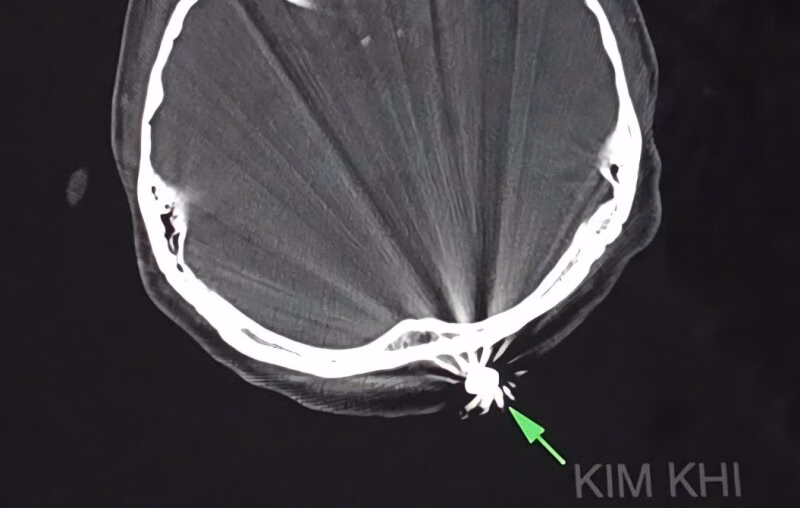

Các bác sĩ Khoa Ngoại thần kinh của bệnh viện đã tiến hành phẫu thuật để lấy dị vật và xử trí tổn thương. Quá trình phẫu thuật, các bác sĩ đã mở rộng vết mổ khoảng 3cm để lấy ra dị vật kim khí là đầu đạn có kích thước 0,5×0,3cm. Ca phẫu thuật diễn ra trong khoảng 45 phút và kết thúc một cách thuận lợi.

Điều đáng chú ý trong trường hợp này là viên đạn chỉ xuyên qua lớp da và chạm nhẹ vào xương chẩm, không gây ra tổn thương đến não và các cấu trúc lân cận. Hiện tại, bệnh nhân tỉnh táo, tiếp xúc tốt, vết mổ khô và không ghi nhận triệu chứng thần kinh khu trú.